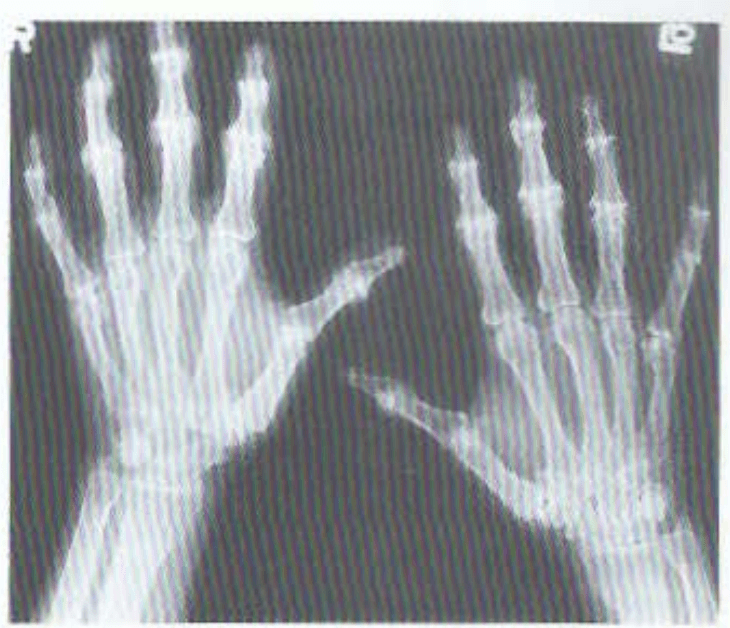

"Hook osteophytes" of particularly the 2nd and 3rd MCP joints, is pathognomonic for this disease

What is hereditary hemochromatosis?

- may also have DIP and PIP involvement